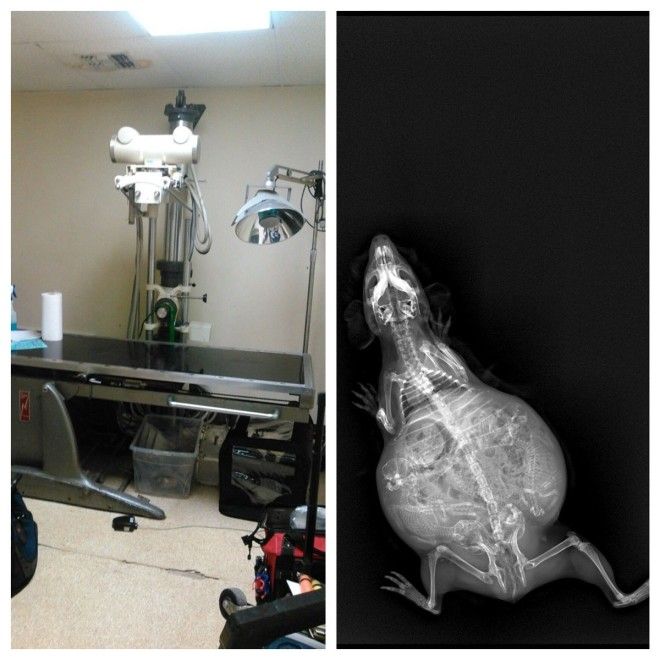

8. Беременная морская свинка